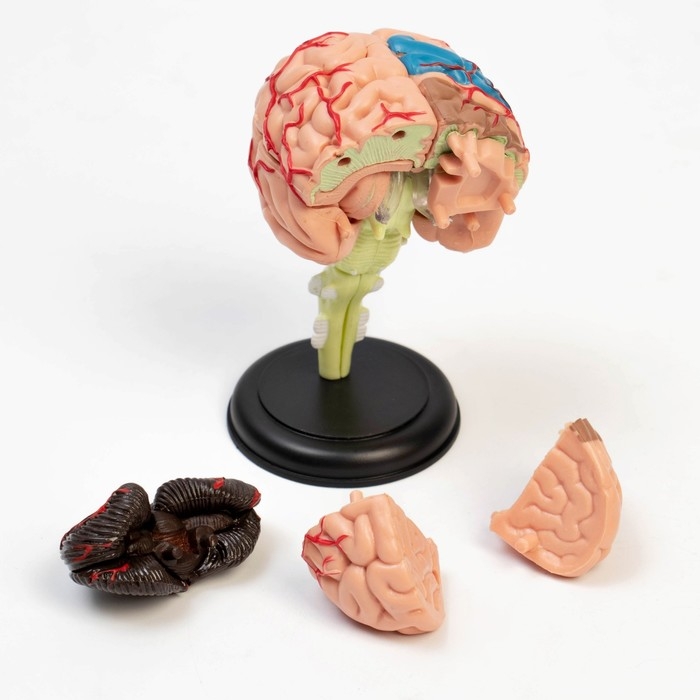

Анатомические модели

ЕКБ 167

No Brand, артикул: 7072352